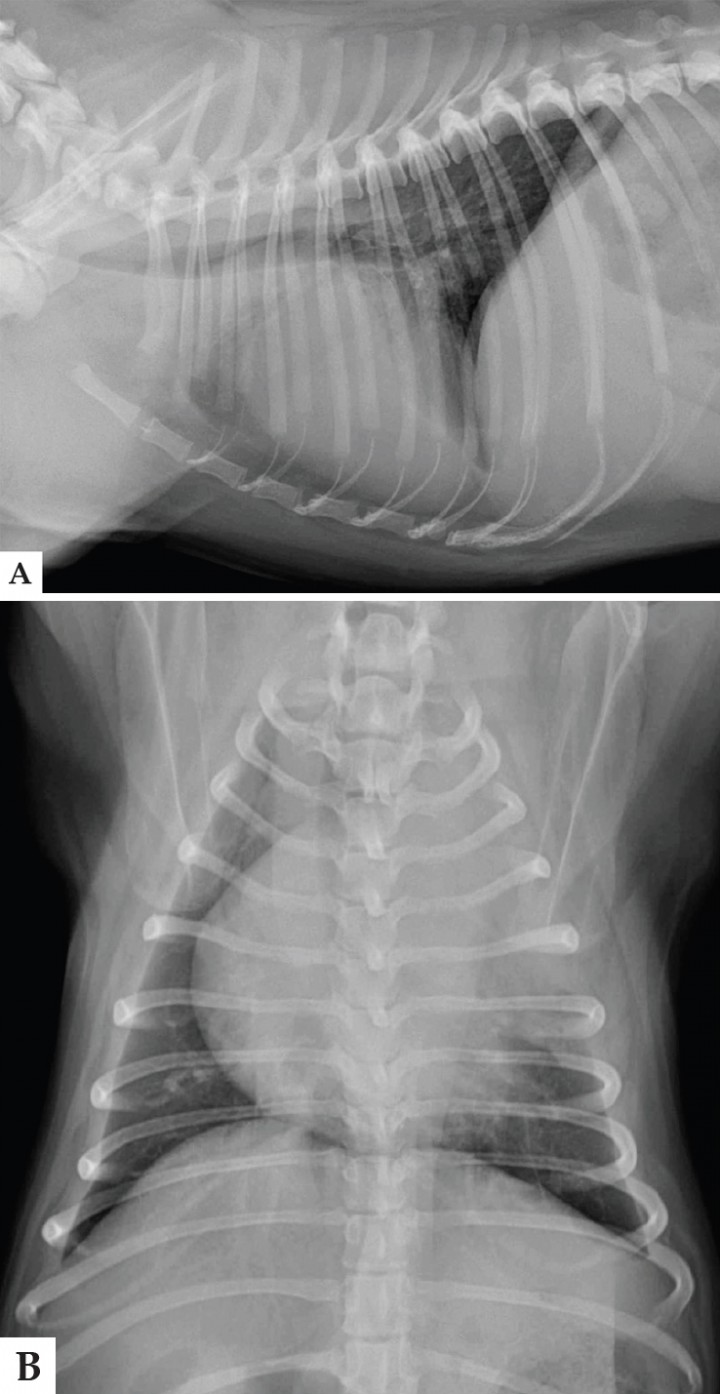

Se observa un aumento de la opacidad pulmonar del lóbulo craneal izquierdo, representado por consolidación en la zona craneal y por un patrón alveolar en la zona caudal, sin desplazamiento de estructuras mediastínicas (Fig. 2). El resto de estructuras intra y extratorácicas no muestran alteraciones radiológicas significativas.

<p>Mismas imágenes que la Figura 1. Se observa un aumento de opacidad pulmonar, consolidación en área craneal y patrón alveolar en área caudal del lóbulo craneal izquierdo (área delimitada en blanco), sin desplazamiento de estructuras mediastínicas. El área círculo negro señala los broncogramas aéreos.</p>

Mismas imágenes que la Figura 1. Se observa un aumento de opacidad pulmonar, consolidación en área craneal y patrón alveolar en área caudal del lóbulo craneal izquierdo (área delimitada en blanco), sin desplazamiento de estructuras mediastínicas. El área círculo negro señala los broncogramas aéreos.